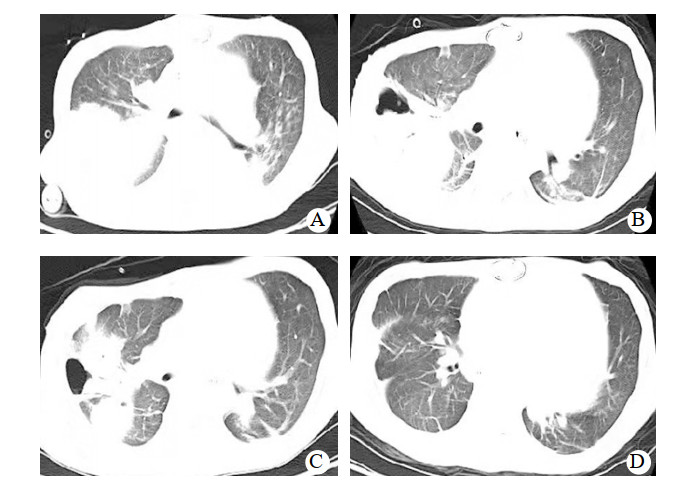

入ICU后查体:血压82/67 mmHg,心率120次/min, 体温36.5℃,呼吸12次/min。双侧瞳孔等大等圆,对光反射迟钝;口唇无发绀,双侧呼吸音粗糙,未闻及干湿啰音。监护提示:窦性心律,心律齐。心前区未闻及心脏杂音;腹平软,肝肋下未触及,肠鸣音弱。四肢末梢皮温正常,足背动脉搏动可及。留置纵隔、心包引流管。入科后即给予了呼吸机辅助呼吸,通气模式采用SIMV/PSV,压力支持12 cmH2O(1 cmH2O=0.098 kPa),呼吸频率12次/min,呼气末正压5 cmH2O, FiO2 0.5,给予舒芬太尼联合右美托咪定镇痛镇静治疗,应用头孢呋辛钠预防切口感染治疗,应用肝素和华法林钠抗凝治疗以及营养支持等综合支持治疗,患者循环稳定,胸片肺淤血较术前减轻,痰不多,于术后第4天顺利脱机拔管,拔管后自主呼吸稳定,少量白稀痰,胸片未见明显变化。术后第7天患者出现体温升高,最高体温38.5℃,痰量增多,为白粘痰,痰中带血,双肺听诊散在痰鸣音,脉搏氧饱和度下降至90%,血气分析提示PaCO2 42 mmHg,PaO2 59 mmHg,实验室检查,PCT 77.87 ng/mL,CRP 198.5 mg/L,患者血压下降,伴有少尿,胸片提示肺感染,经多学科会诊后除外其他部位感染,考虑患者术后合并重症肺炎、呼吸衰竭、感染性休克、急性肾损伤,遂给予再次气管插管机械通气治疗。同时为充分引流痰液,给予了俯卧位通气联合支气管镜肺泡灌洗治疗(俯卧位时间为每次12 h,支气管镜肺泡灌洗每日1次,灌洗剂量为生理盐水100 mL/次),并经验性应用美罗培南联合万古霉素抗感染治疗,给予了液体复苏及CRRT治疗、综合支持治疗。为维持血泵正常运转,继续华林钠口服抗凝治疗,维持INR 2.0~2.5。术后第8天痰培养和血培养均报告为耐碳青霉烯肺炎克雷伯菌,抗生素更改为头孢他啶- 阿维巴坦抗感染治疗。并于术后第15天给患者进行了气管切开治疗。头孢他啶阿维巴坦共应用17 d,期间患者因同时合并了肺部屎肠球菌、热带假丝酵母菌感染,根据药敏实验结果分别给予了替加环素、卡泊芬净等抗感染治疗。因此患者术前反复心衰,营养状况差;术后长期应用抗生素,加上体外循环的打击,机体免疫力差;术后第27天出现菌群失调,严重腹泻,粪便球杆比9 ∶ 1,化验为艰难梭菌感染,给予静脉万古霉素口服(125 mg,q6h)治疗,同时停用所有抗生素。因患者感染未完全控制,继续给予了俯卧位通气联合支气管镜肺泡灌洗治疗,综合营养支持治疗,间断呼吸功能锻炼,患者感染得到有效控制,PCT由77.87 ng/mL下降到0.11 ng/mL,胸片(图 1)及CT(图 2)显示右肺实变影逐渐吸收,术后77 d成功脱离呼吸机辅助,于术后89 d转回普通病房并顺利出院。后期随访患者生活正常。

| 图 2 患者胸部CT变化 |